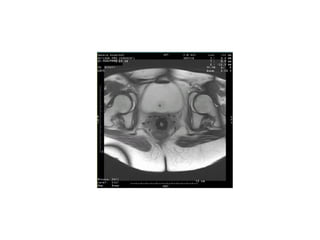

Endometrial cancer